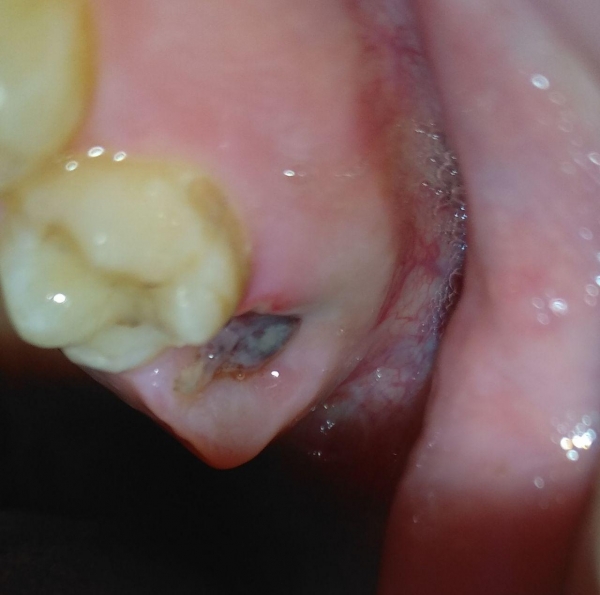

В пятницу утром мне удалили зуб мудрости. Все прошло хорошо, кровь достаточно быстро остановилась, обезболивающих не принимал даже после удаления зуба. Каждый день лунку обрабатывал Хлоргексидином. Болей нет, первые два дня были только ощущения вкуса крови во рту. Сегодня решил посмотреть, как идет заживление, смутил цвет.

Это нормально или похоже на нагноение?

Похоже на фибринозный налет, он сопровождает регенерацию лунки.